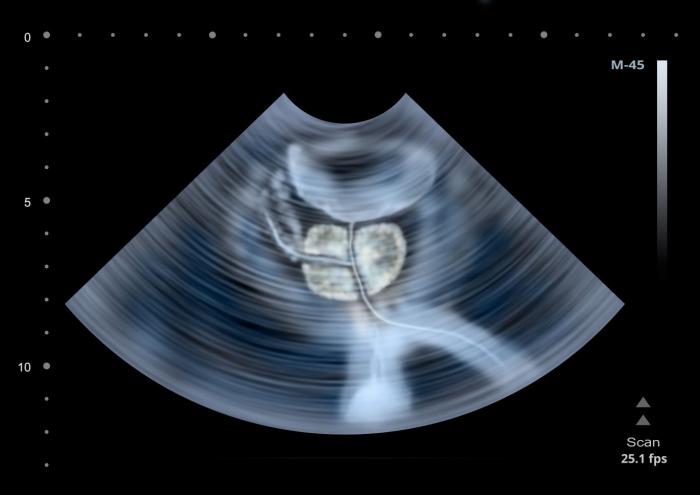

52 éves vagyok. Hasi ultrahangvizsgálat során megnagyobbodott prosztatát találtak. Nincs vizelési panaszom. El kell mennem urológushoz, kell ezt kezelni?

Életkora miatt egyébként is célszerű urológiai szűrővizsgálatra mennie. Amennyiben a vizsgálatok során egyéb eltérést nem találnak, önmagában a megnagyobbodás kezelést nem igényel.